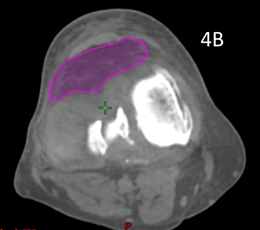

Patient 5 had treatment of a symptomatic left knee. The planning scan showed an effusion measuring 43.0cm3. Three months later the final CBCT of phase one showed a volume of 37.7cm3. A further three months later the final CBCT of phase two showed a volume of 33cm3, an overall decrease of 25%, even though he had increased activity by restarting playing soccer in that time. The reduction from planning CT to the final CBCT is shown in figure is shown in Figure 4. The effusion decreased in volume even though the dose was prescribed to bone. The reduction in the effusion associated with a reduction in symptoms and a better quality QoL points to this effect being more than just placebo as some have opined.

Figure 4 Decrease in size of knee effusion with two phases of 3 Gy in 6 fractions over three months.

Figure 4A Axial planning CT scan through the knee showing effusion coloured in light blue measuring 43.0cm3.

Figure 4B Axial planning CBCT scan taken during the last fraction of Phase 2 through the knee with effusion coloured in purple showing a volume of 33cm3.

Figure 4C Fusion of the above two scans showing significant shrinkage of 25% of the effusion from baseline to end of phase 2.